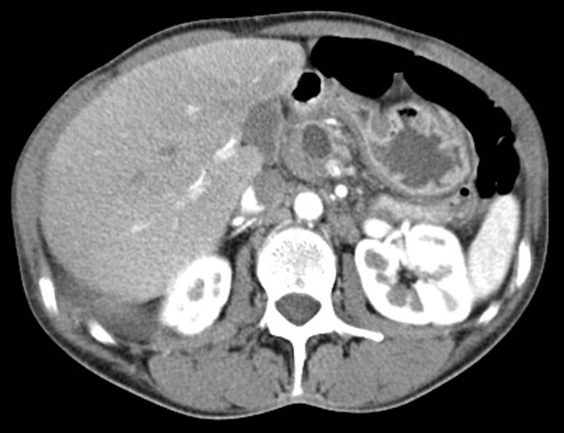

Figure 2. CT abdominal scan showing the persistence of a residual right pleural effusion and two pseudocysts in the head of pancreas

A CT chest and abdominal scan (Figure 2) showed the persistence of a residual right pleural effusion and two pseudocysts in the pancreatic head of 10 and 20 mm respectively.